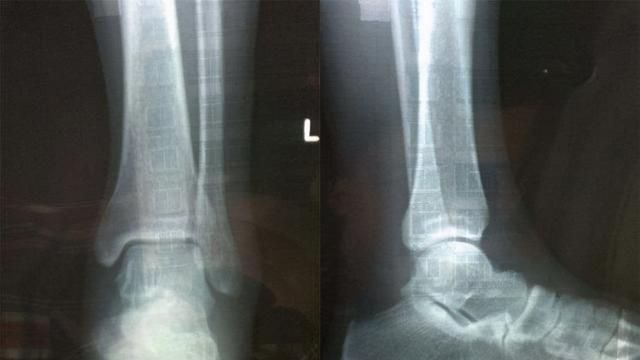

CT检查和是对常规性的检查和,也是较为常用的一类医用,除了磁共振和B超检验。